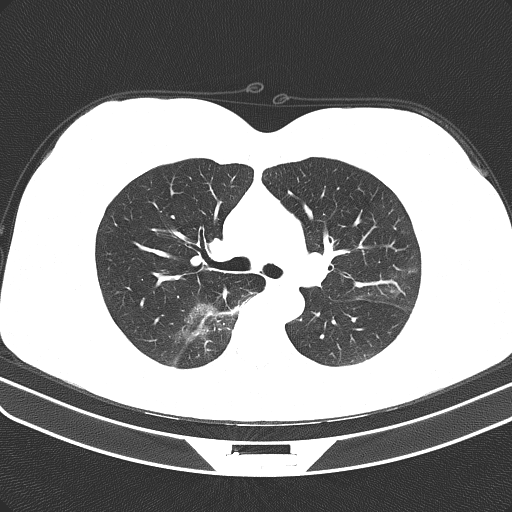

Figure 1 shows four CT scan slices, two from a non-COVID-19 CT scan, on the left and two from a COVID-19 scan, on the right. Bilateral ground glass regions are seen especially in lower lung lobes in the COVID-19 slices.